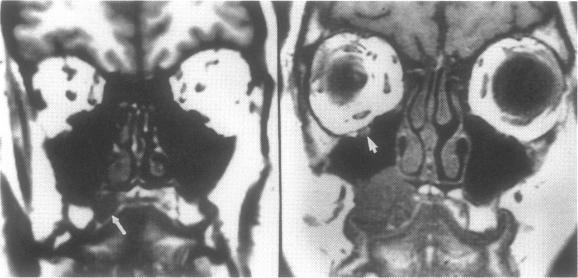

Adenoid cystic carcinoma of the hard or soft palate is a slow-growing, insidious disease with a tendency to spread via a perineural mechanism along the palatine branches of the maxillary division of the trigeminal nerve. Such spread may present first as a tumor in the pterygopalatine fossa or cavernous sinus. The purpose of this manuscript is to report three cases of palatal adenoid cystic carcinoma which presented as a mass in the cavernous sinus prior to discovery of the palate primary tumor. The imaging features of these cases are emphasized as is the need to search for a head and neck primary lesion when faced with a cavernous sinus mass.

硬腭或软腭的腺样囊性癌是一种生长缓慢、隐匿性疾病,有通过神经周围机制沿三叉神经上颌支的腭支扩散的倾向。这种扩散最初可能表现为翼腭窝或海绵窦内的肿瘤。本文的目的是报告三例腭腺样囊性癌病例,这些病例在发现腭部原发肿瘤之前,表现为海绵窦内的肿块。强调了这些病例的影像学特征,以及面对海绵窦肿块时寻找头颈部原发病变的必要性。